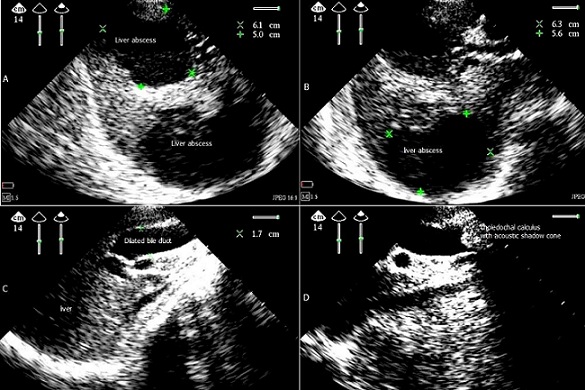

The annual incidence of non-parasitic liver abscess is low with 2.3 per 100 000. The biliary abscesses are usually secondary to biliary obstruction; with gallstones is by far the most common. In ultrasound, the early phase: abscess may appear hyperechoic, the liquefaction phase: anechoic with internal echoes, contours are usually irregular. The treatment of abscess hepatic are based on the puncture echo guided, and by broad-spectrum antibiotics guided by susceptibility of germ, surgical treatment is reserved for failures puncture, if not endoscopic sphincterotomy. We report a woman aged 85 years, coronary heart disease followed for his five years with ejection fraction 35%, cholecystectomized seven years ago, admitted to the ICU for fever, pain right upper quadrant. Abdominal ultrasound showed a dilated principal bile duct to 1.7 cm diameter with gallstone a 1.8/1.7cm, two liver images: segment VII and V with 6.1/5cm and 6.3/5.6 cm diameter, fuzzy aspects, without clear boundary with the liver parenchyma, with an anechoic center associated with some hyperechoic image in favor of liquefaction abscess stage, of biliary origin. Amoebic serology was negative. The drainage echo guided was made with empirical antibiotic, and guided after by a susceptibility which the germ was a streptococcus. The patient was referred for possible endoscopic sphincterotomy after seven days, given the high anesthetic risk for surgical drainage of the bile duct.